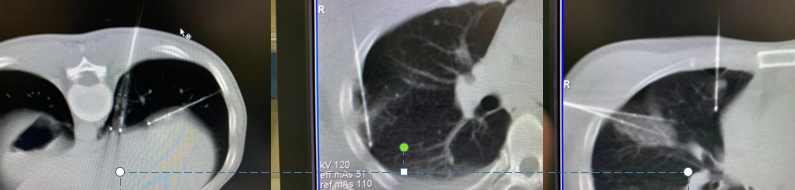

▲这是一位肝癌肺转移患者,肺上有6个结节,考虑年纪较轻,身体状况尤其是肺功能良好,利用冷冻消融一次性解决6个肺结节,避免二次创伤,也减轻经济负担。